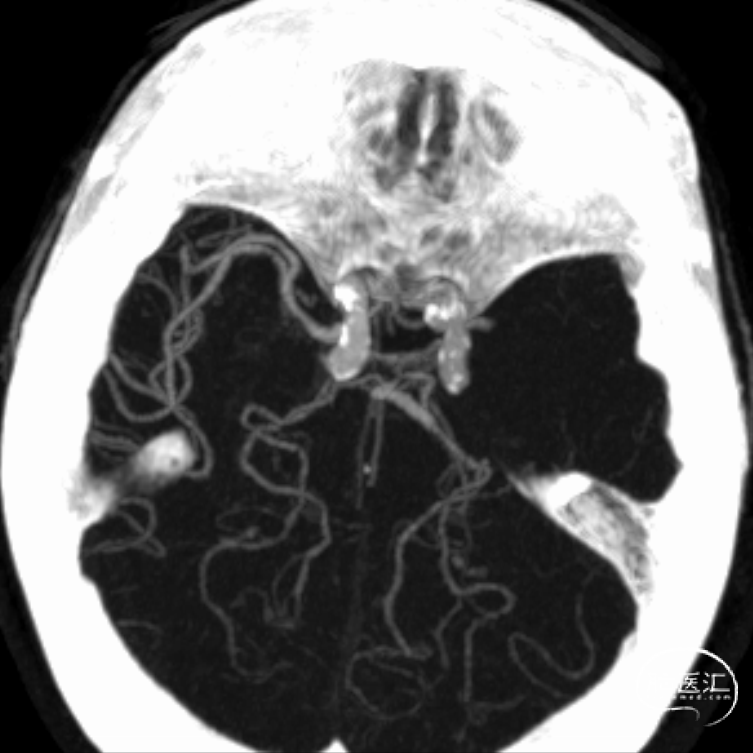

动脉早期水平位残端

动脉晚期冠状位脑膜支逆流

CTA

多模式影像学评估可协助血管闭塞性质的判断,特别是多时相CTA扫描;